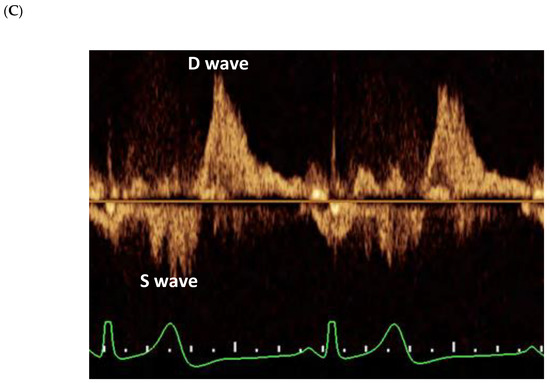

3.2. Pulmonary Venous Flow Pattern